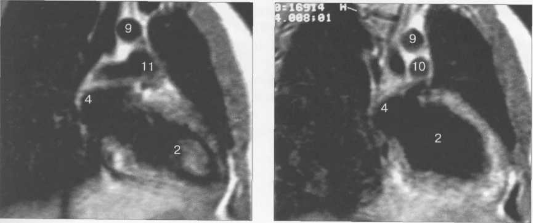

Рис. 9.47. МРТ сердца. Аксиальная плоскость.

Здесь и на рис. 9.48—9.52:

I — правый желудочек, 2 — левый желудочек, 3 — правое предсердие, 4 — левое предсердие, 5 — межжелудочковая перегородка, 6 — межпредсердная перегородка, 7 — задняя стенка левого желудочка, 8 — восходящая часть аорты, 9 — дуга аорты, 10 — нисходящая часть аорты, 11 — легочный ствол, 12 — правая легочная артерия. 13 — левая легочная артерия, 14 — верхняя полая вена, 15 — нижняя полая вена, 16 — трахея.

Рис. 9.48. MPT сердца. Сагиттальная плоскость.

Рис. 9.49. МРТ сердца. Двухкамерные сечения.

Рис. 9.50. МРТ сердца. Фронтальные сечения.

Рис. 9.51. МРТ сердца. Сечения по короткой оси левого желудочка.

Рис. 9.52. МРТ сердца. Четырехкамерные сечения.

На рис. 9.47—9.52 представлены Т1-ВИ наиболее часто используемых МР-сечений сердца.